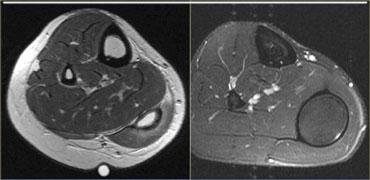

Bên trái là hình ảnh bệnh nhân bị tổn thương cơ bụng chân độ 2.

Có tổn thương độ thấp ở đầu ngoài.

Bên trái là cùng một bệnh nhân.

Cũng có tổn thương mức độ trung bình ở đầu trong.

Lưu ý các ổ tích tụ dịch xung quanh đầu cơ.

Dịch càng nhiều, mức độ tổn thương càng cao.

Bên trái là cơ thẳng đùi bị tổn thương.

Các hình ảnh cho thấy tổn thương mức độ vừa, với sự biến dạng cấu trúc và một ổ tụ dịch (mũi tên).

Lưu ý phù nề tại chỗ nối cơ-gân dạng hai lông chim.